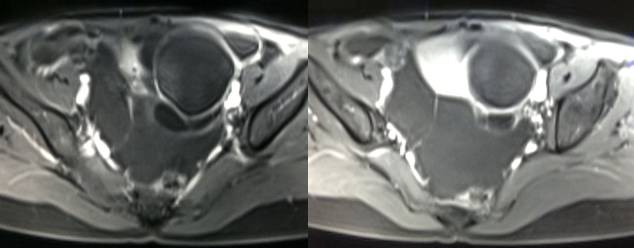

MR检查:

病理结果:黄体血肿

黄体血肿早期:囊内出血较多时,表现为卵巢内近圆形囊肿,囊壁厚,内壁粗糙。

黄体血肿中期:黄体血肿内血液凝固,部分吸收,囊壁变薄而,内壁光滑。

黄体血肿晚期:血液吸收后囊肿变小,转折为白体,内部回声呈实性稍高回

声,与周围卵巢组织分界不清,面靠彩超显示其周围环状血流判断,当血液完全吸收后形成黄体囊肿,囊壁变得光滑,与卵巢其他囊肿难以区分。

根据时间不同MR信号也有所不同,TIWI脂肪抑制序列可以鉴别脂肪和出血。